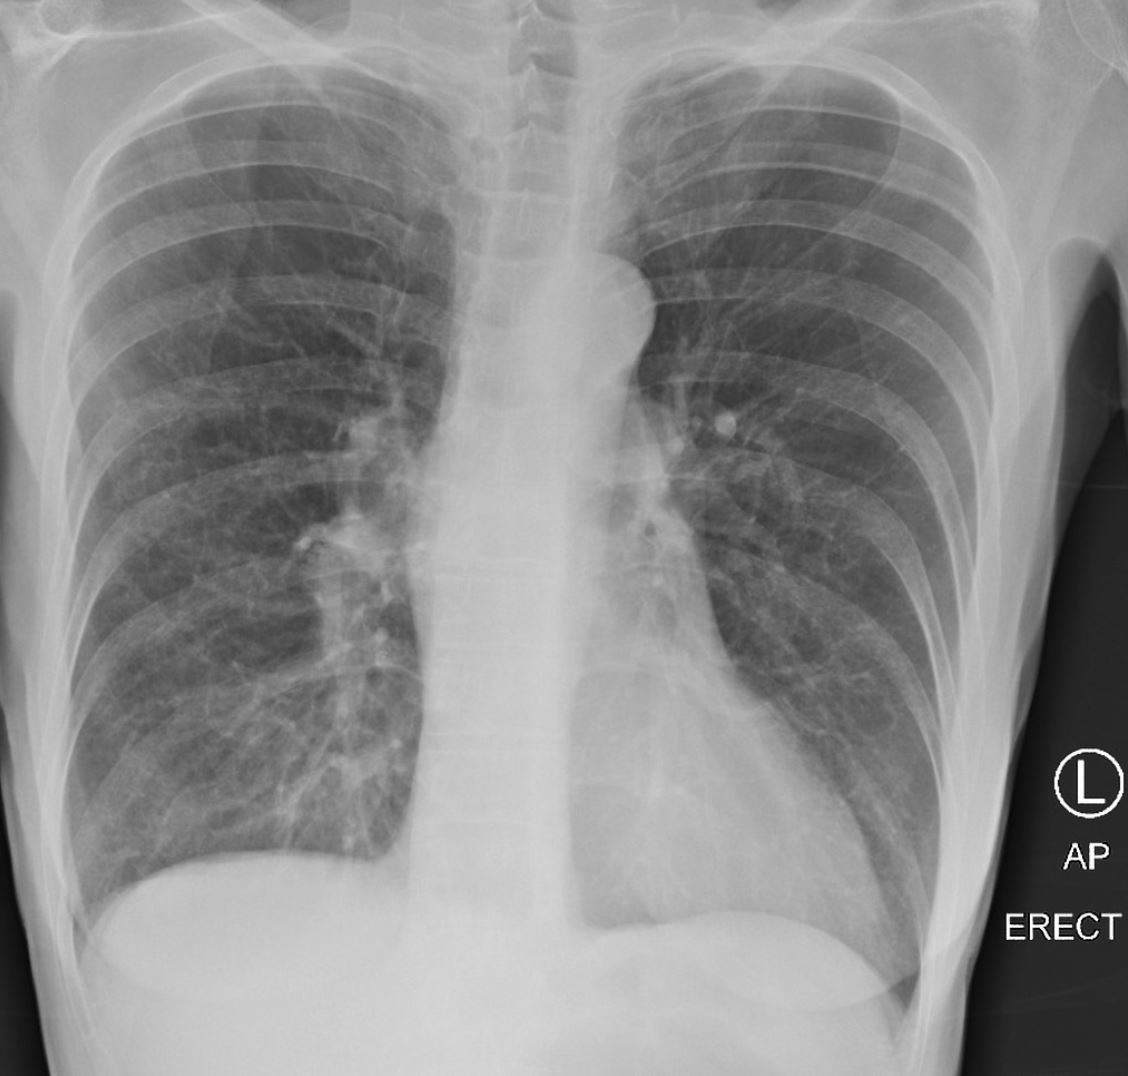

CXR signs of COPD

Acute

Consolidation

Pneumothorax

Chronic

Hyperinflation

Pulmonary HTN

Bullae